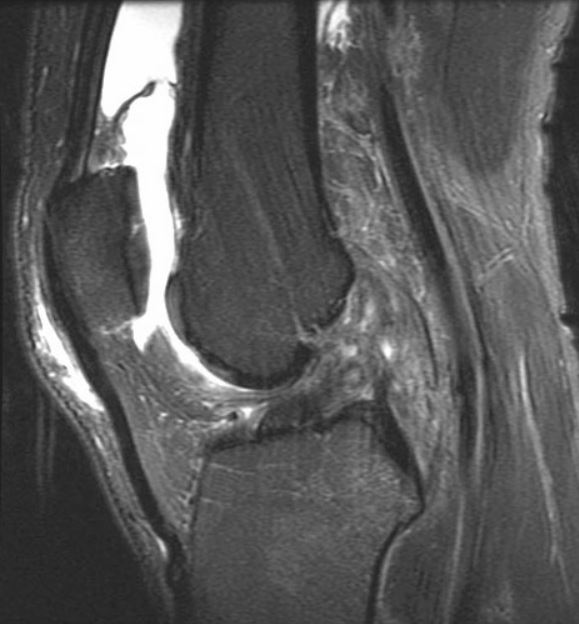

#CaseOfTheWeek🎉 📢✅Answer for Case #30: #Sign🟰Segond fracture & #Diagnosis🟰Torn ACL🦴🦵 Stay tuned for next week's Case #31 and have a great weekend!!🥳🎉 #FOAMrad #RadEd #OrthoTwitter SSR_RWG @UWRadRes #MedEd #OrthoSports @AOSSM_SportsMed

#CaseOfTheWeek🎉

📢✅Answer for Case #30: #Sign🟰Segond fracture &amp; #Diagnosis🟰Torn ACL🦴🦵